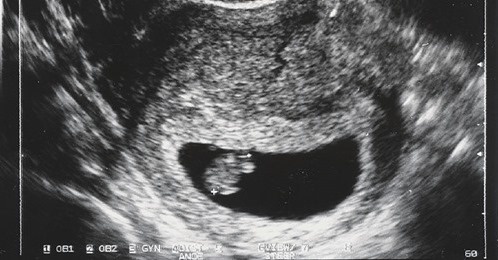

В штате Теннесси хотят разрешить биологическим отцам запрещать беременным женщинам сделать аборт.

В штате Теннесси хотят внести законопроект, который позволит биологическим отцам запретить женщине, которая беременна своим еще не родившимся ребенком, сделать аборт.